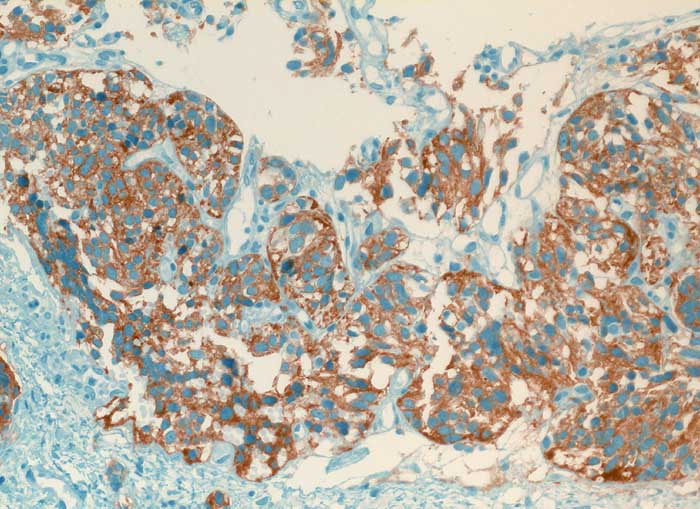

Karzinoid

Lunge

Die spindeligen Tumorzellen exprimieren den endokrinen Marker Synaptophysin.

Synaptophysin